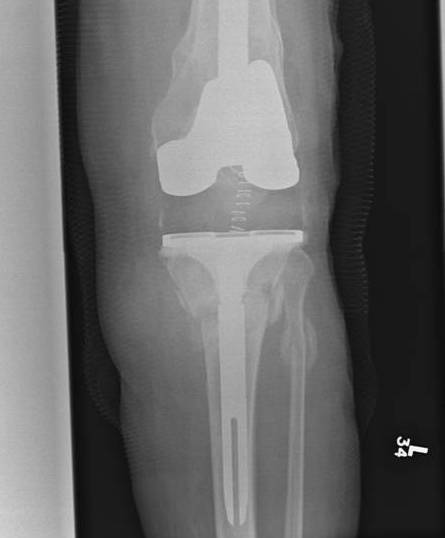

2.  Retrograde IM Nail

TKR Periprosthetic FractureTKR Periprosthetic Fracture 2TKR Periprosthetic Fracture Retrograde Nail 1TKR Periprosthetic Fracture Retrograde Nail 2

Issue

May be biomechanically superior

Have to open TKR to perform operation

- risk deep infection

Indications

Technically feasible

- CR knees contra-indicated

- must have sufficient sized hole in PS femoral component

- consult company as to suitablity

- small diameter nail

Technique

Minimum intercondylar distance of 12 mm

- AGC 18MM

- PFC = 20MM

- Genesis = 20MM

Usually remove polyethylene component

- replace after nail

- usually need new poly